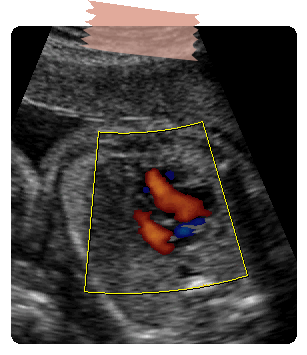

Cardiopatia congénita más frecuente, hay un defecto interventricular, generalmente perimembranoso, aorta que cabalga sobre el septum interventricular.

En el corte de 3 vasos se puede diferenciar si hay estenosis, atresia o ausencia válvula pulmonar